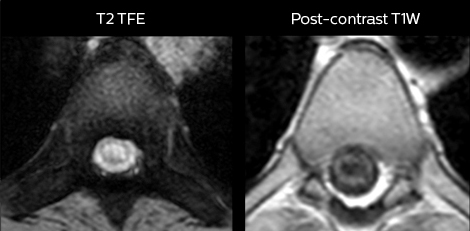

To minimize the time taken to perform scans, rapid MRI examination protocols (ExamCards) were developed, shortening the total scanning time to even less than 10 minutes in some exams. Techniques like mDIXON (modified DIXON) are used for robust capturing of fat-free MRI images in a hectic ED environment.

“We use mDIXON TSE extensively in our spine imaging in the emergency room,” says Dr. Karis. “It’s particularly nice in that it is very robust with regard to susceptibility type of problems that would come up with traditional spectral fat-saturated images; these problems are essentially eliminated with the mDIXON technique. In our ED environment it’s really nice to have the fat-free imaging that goes along with the mDIXON technique.

“For the thoracic and cervical spine routine non-contrast exam, for example, we perform one mDIXON T2 TSE sequence, which provides us with two outputs: the fat-and-water-together T2-weighted images, as well as the water-only sagittal T2-weighted images. And then we also perform an axial gradient echo exam.”